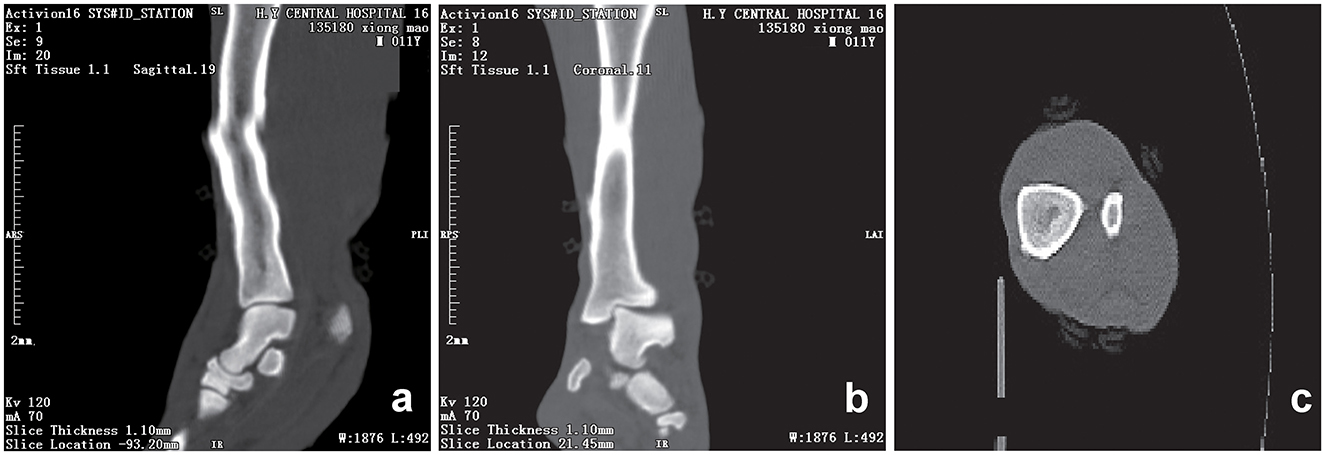

Initial clinical evaluation involved observation and palpation of the limbs, followed by blood collection for routine hematological and biochemical testing. A non-anesthetic examination revealed mild atrophy of the left hind limb, with no pain response on palpation. There was mild alopecia on the medial aspect of the left hind limb's thigh and increased skin temperature, without detected swelling, trauma, or joint deformity. Additionally, claw abrasion was noted on the right paw, accompanied by erythema and swelling of the right paw pad (Figure 1b). No other abnormalities were detected during this initial assessment. Blood samples were collected concurrently for routine blood and biochemical tests, which subsequently revealed low lymphocyte and platelet counts, and the levels of total cholesterol (TC) and triglycerides (TG) were elevated. However, no significant increase in C-reactive protein (CRP) was observed (since there was no reference range for CRP in giant pandas, human levels were used here; Table 1). Throughout this examination phase, the panda's diet and weight remained stable, consistent with its baseline status. 3 days later, under general anesthesia, further examination was performed. The panda's body temperature was normal, and no external injuries, or draining fistulas were observed. Subsequently, advanced imaging modalities were employed. Non-enhanced scanning of both hind limbs was performed using a Toshiba Activion 16 multislice CT scanner (TOSHIBA, Tokyo, Japan). The panda was placed in a dorsal recumbency. The scanning protocol included both hindlimbs, extending from the femur to the phalanges. A helical scan mode was used with a gantry rotation time of 0.5 s per rotation and a detector configuration of 16 rows × 1.0 mm. The beam collimation width was matched to the detector configuration (16 × 1.0 mm), with an original slice thickness of 1.0 mm. Tube voltage was set at 120 kV and tube current at 70 mA. The pitch was 1.375:1. The scan field of view (SFOV) was adjusted according to the number of hind limbs: 450 mm for bilateral and 400 mm for unilateral examinations. The Z-axis scanning range was ~600 mm, and the original slice thickness was fixed at 1.0 mm. Image reconstruction parameters were tailored to diagnostic needs. For bone evaluation, images were reconstructed with a slice thickness of 5.0 mm. For soft tissue evaluation, images were reconstructed with a slice thickness of 1.1 mm and a reconstruction interval of 0.69 mm. A high-resolution bone algorithm (Bone 5.0) was applied for bone reconstruction, and a standard soft tissue algorithm (Soft Tissue 1.1) was applied for soft tissue reconstruction. The reconstruction matrix was uniformly 512 × 512, with a pixel size of 0.8 mm. The display field of view (DFOV) was set to 350 mm. For the bone window, window width and level were 2,000 HU and 500 HU, respectively; for the soft tissue window, window width and level were 1,876 HU was 492 HU, respectively. CT scans revealed no evidence of fractures, joint space narrowing or widening, osteophyte formation, or other bony abnormalities in either hind limb (Figure 2). With the permission of the government, these CT scans were read jointly by radiologists and veterinarians, who confirmed that there were no osseous abnormalities in the two hind limbs. Following the CT examination, a Toshiba Vantage Titan 1.5T MRI (TOSHIBA, Tokyo, Japan) was used to perform MRI examinations. Image acquisition is carried out with a slice thickness of 3–5 mm and an interval of 1–2 mm. First, conventional SE sequences were used for image acquisition (T1W: TR 1,700 ms, TE 15 ms); T2W: TR 4,294 ms, TE 105 ms). T1W sagittal images of the tarsus show that the bony structures, including the distal tibia, talus, and calcaneus, have distinct and well-defined margins. The bone marrow signal within these bones is homogeneous, with no apparent abnormal hypointense or hyperintense areas detected. The articular cartilage of the tarsus maintains a smooth surface, and its signal intensity on T1W imaging is consistent with that of normal articular cartilage, appearing isointense relative to the adjacent muscle tissue in most regions. The tarsus ligaments, such as the dorsal talofibular ligament and calcaneofibular ligament (visualized in appropriate sections), exhibit normal low–signal characteristics on T1W sequences, without evidence of discontinuity, thickening, or abnormal signal intensity. The surrounding soft tissues, including the tendons (e.g., the Achilles tendon, tibialis cranial) and the joint capsule, display a normal layered structure, with no significant swelling, thickening, or abnormal signal intensity changes. The T2W transverse image shows that patchy high signals are found in the soft tissues around the distal tibia and the plantar aspect of the tarsus calcaneus, with indistinct edges. The signal intensity is higher than that of the adjacent normal muscle tissue. The high intensity around the distal tibia is mainly located in the interosseous space or interosseous muscle on the inner side of the distal tibia. The high signal plantar calcaneus is mainly distributed around the subcutaneous soft tissue on the inner, outer and plantar sides of the Achilles tendon (Figure 3). At the same time, there are also some high signal intensities in soft tissues of the plantar aspect of tarsus. Based on MRI findings, a diagnosis of osteomyelitis in the left hindlimb was made.

Figure 2. CT scans of the hind limb of the giant panda. Sagittal (a), coronal (b) and transverse (c) computed tomography (CT) scan of the left hind limb showing smooth, well-defined articular margins. The tarsal bones are correctly aligned, and corticomedullary definition is normal. The distal tibial articular surface shows a normal inclination angle. No fractures are observed. The osseous structures of the included joints are intact with no adjacent significant soft tissue swelling. A slight step artifact is present in the mid and distal diaphysis of the tibia. Scan parameters: tube voltage = 120 kV; tube current = 70 mA; slice thickness = 1.10 mm; window width (WW) = 1,876 HU; window level (WL) = 492 HU; reconstructed using a soft tissue 1.1 sequence.